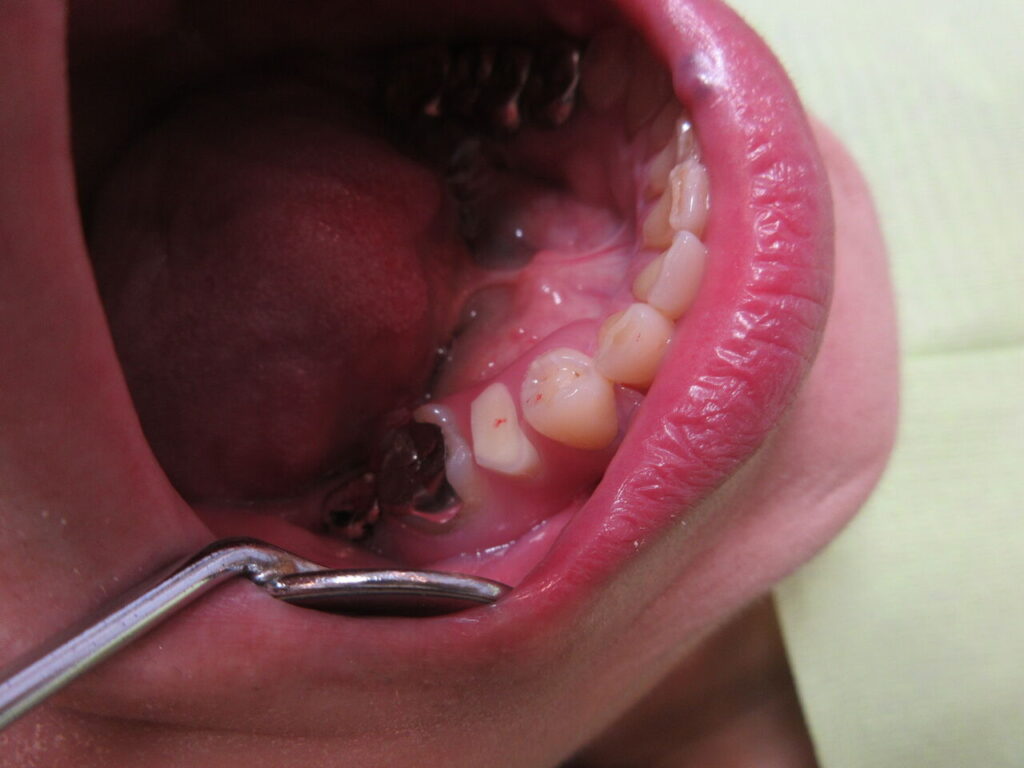

ブリッジもインプラントも希望されない患者様にノンクラスプデンチャーを装着。

薄く目立たないのが最高です。